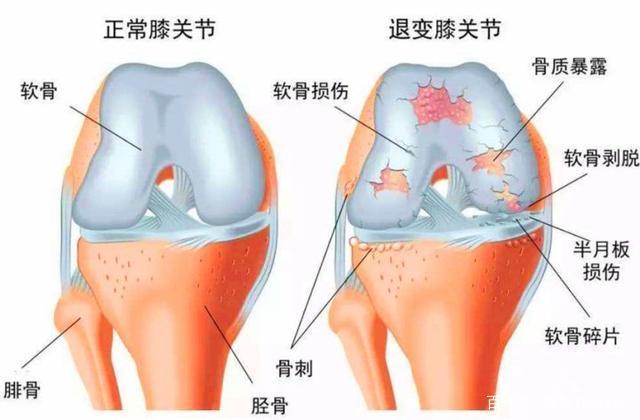

以“膝关节退变”简单举例说一下,我们人每天都要走很多路,膝关节不停地反复弯曲伸直,青壮年身体机能良好,可以很好的恢复,随诊年龄增长,机体机能逐渐下降,肌肉力量下降,关节韧带松弛,关节软骨老化,进而引起膝关节的不稳定和异常活动。

膝关节不稳定和异常活动造成膝关节的应力异常,出现骨膜下出血,水肿和无菌炎症,出血中的骨膜细胞,间充质细胞等在细胞因子的作用下向骨细胞分化,从而骨化形成骨质增生,以此来限制关节的异常活动,进而维持关节的稳定。从这个角度来讲,骨质增生就是关节不稳的修复反应,是机体的自我保护性反应。只是在这个修复过程中,受到多种因素的影响,增生没能达到完全修复的目的,反而出现压迫神经或其他器官而引起临床症状。